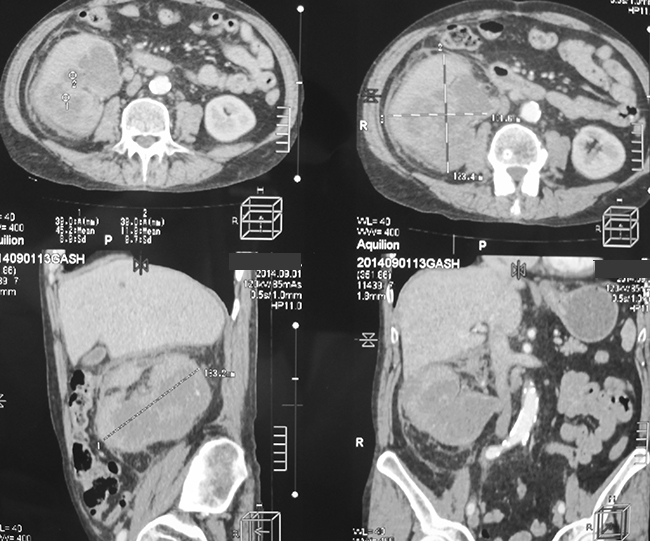

ФОТО дня